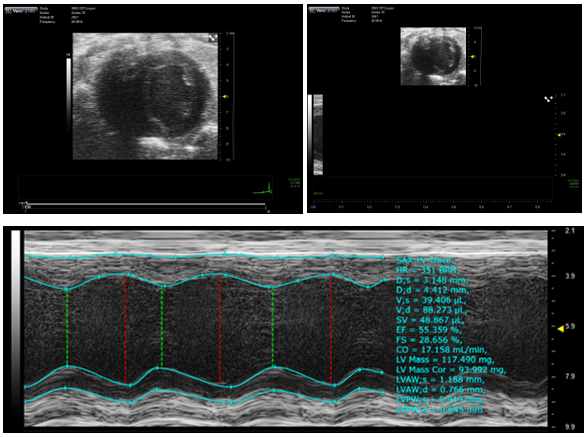

Ultrasound

Visualsonics Vevo 2100

- Up to 30 micron resolution and framerates up to 740 fps

- Echocardiography

- Ejection Fraction

- Fractional Shortening

- Stroke Volume

- Color and Power Doppler Modes for blood flow quantification

- Anatomic Imaging

- 4D Imaging (3D + ECG-gated Time)